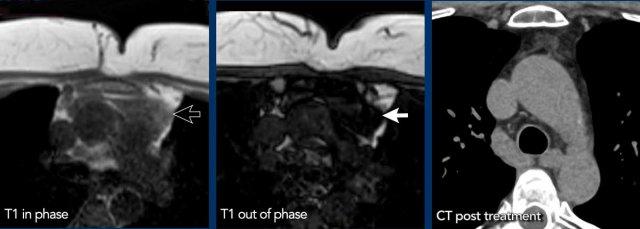

Chỉ số cường độ tín hiệu

Chỉ số cường độ tín hiệu (SII) là lượng tín hiệu bị mất đi chia cho lượng tín hiệu ban đầu.

SII lớn hơn 9% có độ nhạy và độ đặc hiệu 100% trong chẩn đoán tăng sản tuyến ức.

SII đáng tin cậy hơn so với tỷ số dịch chuyển hóa học.

Trong trường hợp này, SII là 77%.

Ca lâm sàng 2

Đây là một ca lâm sàng khác.

Tín hiệu giảm từ 130 xuống còn 77.

Điều này có nghĩa là chúng ta đang đối diện với mô tuyến ức.